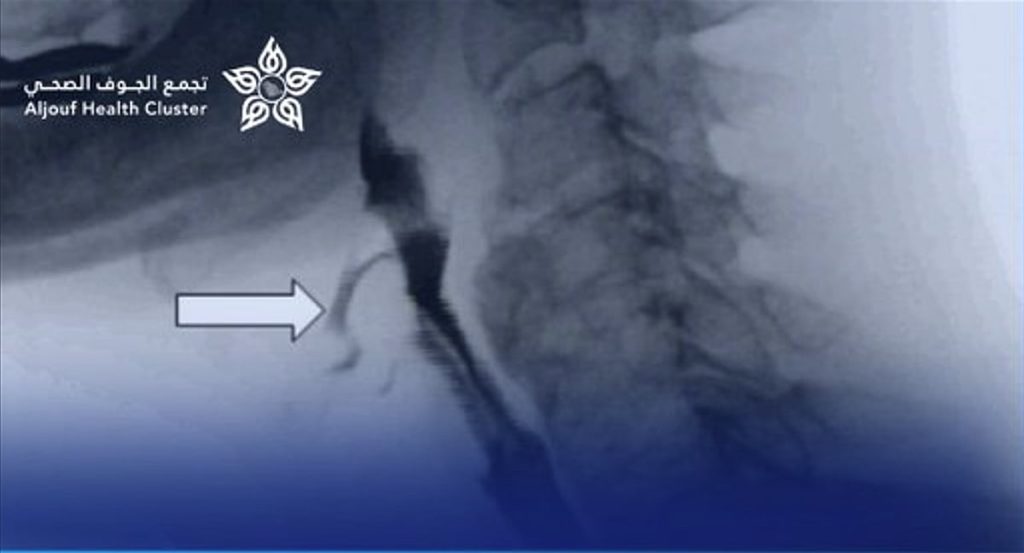

وأوضح التجمع الصحي بمنطقة الجوف أن الطفل كان يعاني من صعوبة شديدة في البلع واسترجاع متكرر للطعام، وتبيّن بعد الفحوصات وجود تضيق شديد في المريء يعيق مرور الطعام. وقد قام الفريق الطبي بإجراء عملية توسيع للتضيق باستخدام المنظار والموسعات الطبية المناسبة، تكللت بالنجاح الكامل دون أي مضاعفات.

وأشار التجمع إلى أن حالة الطفل تحسّنت بشكل ملحوظ بعد العملية، وتمكن من تناول الطعام بصورة طبيعية، وغادر المستشفى بعد يومين من الإجراء وهو في صحة جيدة.